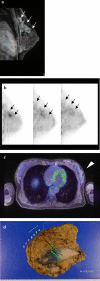

Background: Dedicated breast positron emission tomography (dbPET) has been developed for detecting smaller breast cancer. We investigated the diagnostic performance of dbPET in patients with known breast cancer.

Methods: Eighty-two preoperative patients with breast cancer were included in the study (84 tumours: 11 ductal carcinomas in situ [DCIS], 73 invasive cancers). They underwent mammography (MMG), ultrasonography (US), and contrast-enhanced breast magnetic resonance imaging (MRI) before whole-body PET/MRI (WBPET/MRI) and dbPET. We evaluated the sensitivity of all modalities, and the association between the maximum standard uptake value (SUVmax) level and histopathological features.

Results: The sensitivities of MMG, US, MRI, WBPET/MRI and dbPET for all tumours were 81.2% (65/80), 98.8% (83/84), 98.6% (73/74), 86.9% (73/84), and 89.2% (75/84), respectively. For 11 DCIS and 22 small invasive cancers (≤ 2 cm), the sensitivity of dbPET (84.9%) tended to be higher than that of WBPET/MRI (69.7%) (p = 0.095). Seven tumours were detected by dbPET only, but not by WBPET/MRI. Five tumours were detected by only WBPET/MRI because of the blind area of dbPET detector, requiring a wider field of view. After making the mat of dbPET detector thinner, all 22 scanned tumours were depicted. The higher SUVmax of dbPET was significantly related to the negative oestrogen receptor status, higher nuclear grade, and higher Ki67 (p < 0.001).

Conclusions: The sensitivity of dbPET for early breast cancer was higher than that of WBPET/MRI. High SUVmax was related to aggressive features of tumours. Moreover, dbPET can be used for the diagnosis and oncological evaluation of breast cancer.